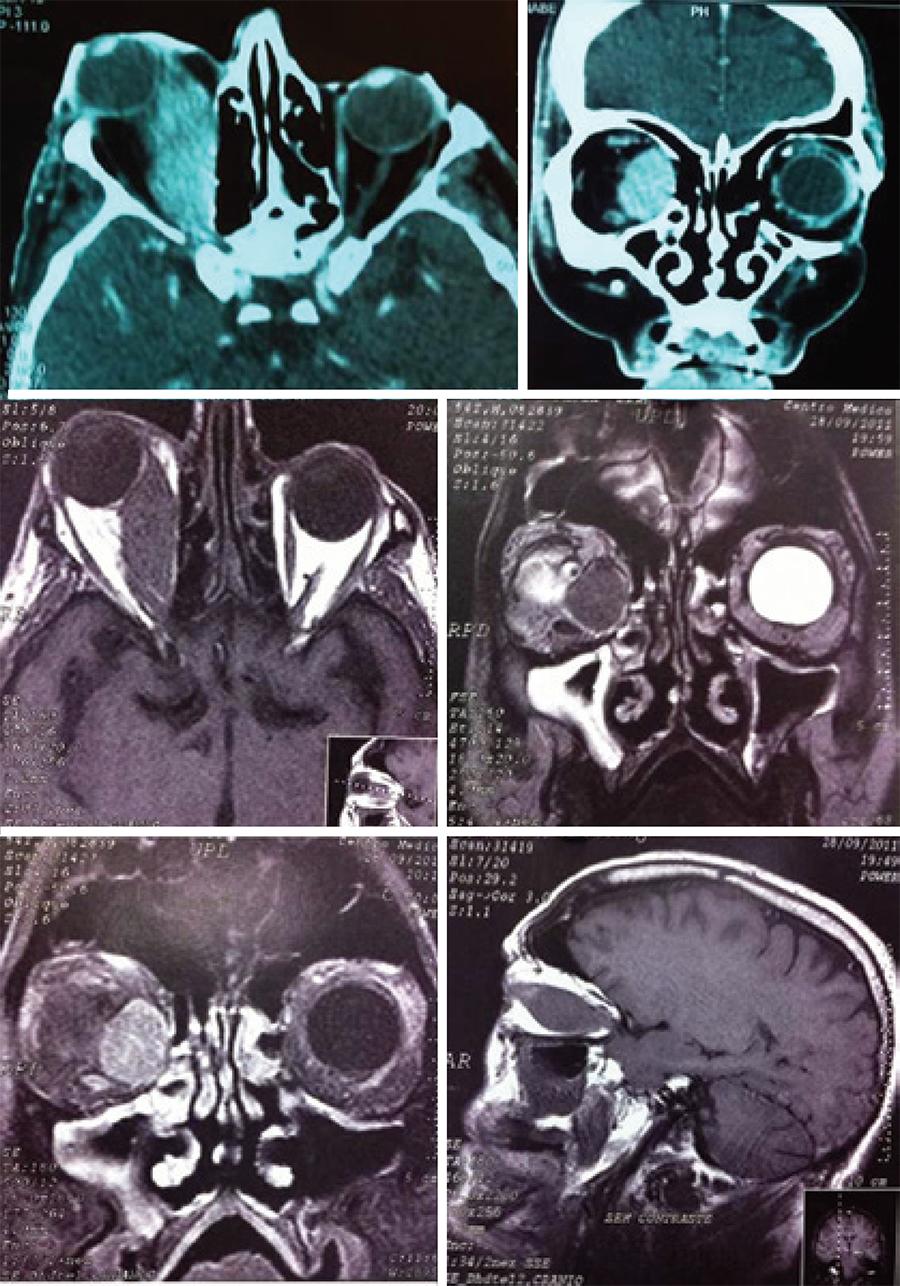

A 55-year-old presented with progressive eye pain and low visual acuity in the right eye since 2 years. His past medical history was unremarkable, and he denied the use of any medications. He had previously undergone treatment for glaucoma in both eyes with travaprost and brimonidine. During the ophthalmologic examination, his visual acuity was 20/70 in the right eye and counting fingers at 1.5 m in the left eye. The right eye exhibited proptosis (exophthalmometry base 100 = 31 mm in the right eye and 14 mm in the left eye), which was associated with chemosis, conjunctival hyperemia, lower eyelid retraction, exotropia, and ocular motility limitation (Figure 1). There was no palpable regional lymphadenopathy. According to Goldmann tonometry, his intraocular pressure was 32 mmHg in the right eye and 30 mmHg in the left eye. Fundoscopy revealed a cuptodisc ratio of 0.9 × total in the right eye and 0.7 × 0.8 in the left eye, with no other changes. Computed tomography (CT) and magnetic resonance imaging (MRI) of the orbit showed a significantly larger fusiform medial rectus muscle in the right eye, with tendon involvement (Figure 2).

Figure 2 Computed tomography (two photos above) and magnetic resonance imaging (four photos below) of the orbit show that the optic nerve is deflected upward and to the side, with fusiform enlargement of the right medial rectus muscle in full extension, tendon involvement, no damage to the bones of the orbital wall, and no signs of cortical erosion

Imaging studies such as CT and MRI allow for the observation of the increased thickness of the affected muscle and tendon involvement. This information, together with the clinical signs and pathology, can confirm the diagnosis. In our patient, imaging studies revealed tendon involvement, which suggested a differential diagnosis of Graves' ophthalmopathy. In imaging studies, other characteristics of thyroid ophthalmopathy that may be observed include welldefined fusiform enlargement of the muscle (especially posteriorly) with smooth borders, no tendon enlargement, normal orbital fat, preseptal edema, and lacrimal gland prolapse(3).